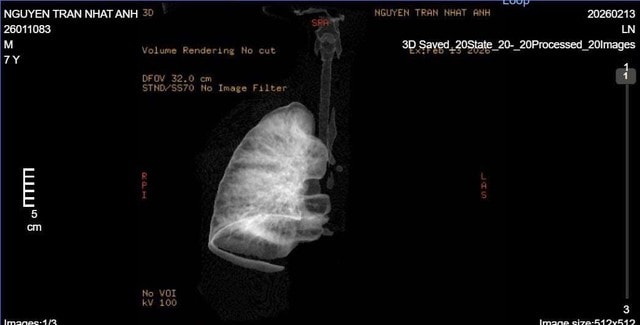

Kết quả chụp CT phát hiện dị vật kích thước khoảng 5x6mm nằm trong phế quản gốc trái, cách carina 6mm, bít kín hoàn toàn lòng phế quản. Trường phổi trái giảm thể tích, đông đặc toàn bộ – dấu hiệu xẹp hoàn toàn phổi trái do dị vật đường thở.

Hình ảnh CT cho thấy toàn bộ phổi trái xẹp do dị vật bít kín phế quản gốc trái.